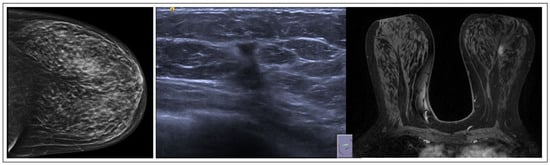

On MRI, PLs typically manifest as circumscribed, solid enhancing lesions; however, they may also exhibit irregular shapes and indistinct margins [13] (Figure 2). These lesions have a benign papillary structure with fibrovascular cores and benign epithelium, often classified as B3 due to potential variations.

Figure 2. PL radiological features.